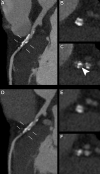

CT systems equipped with photon-counting detectors (PCDs), referred to as photon-counting CT (PCCT), are beginning to change imaging in several subspecialties, such as cardiac, vascular, thoracic, and musculoskeletal radiology. Evidence has been building in the literature underpinning the many advantages of PCCT for different clinical applications. These benefits derive from the distinct features of PCDs, which are made of semiconductor materials capable of converting photons directly into electric signal. PCCT advancements include, among the most important, improved spatial resolution, noise reduction, and spectral properties. PCCT spatial resolution on the order of 0.25 mm allows for the improved visualization of small structures (eg, small vessels, arterial walls, distal bronchi, and bone trabeculations) and their pathologies, as well as the identification of previously undetectable anomalies. In addition, blooming artifacts from calcifications, stents, and other dense structures are reduced. The benefits of the spectral capabilities of PCCT are broad and include reducing radiation and contrast material dose for patients. In addition, multiple types of information can be extracted from a single data set (ie, multiparametric imaging), including quantitative data often regarded as surrogates of functional information (eg, lung perfusion). PCCT also allows for a novel type of CT imaging, K-edge imaging. This technique, combined with new contrast materials specifically designed for this modality, opens the door to new applications for imaging in the future.